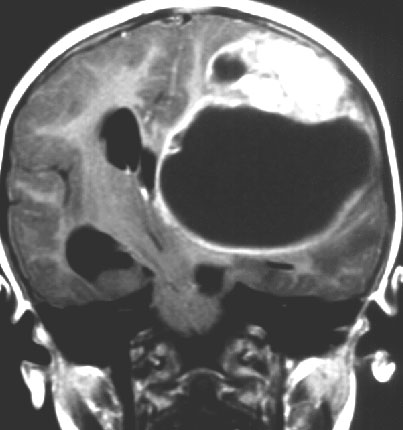

- 大脳の表面にできて,とても大きな腫瘍で,大きなのう胞(液体がたまる)を伴います

- 腫瘍の特徴は,乳児の大脳の表面にある巨大な腫瘍です

- 液体のたまっているのう胞が大部分です

- 不正形に造影剤で増強されて白く映る塊が見えますが,それが本体です

- 頭頂葉と前頭葉表面に広がり数センチを越える巨大なのう胞性腫瘍となります

- 大脳深部方向へ食い込むのう胞があり,固形腫瘍部分は結節様に表在することが多いです